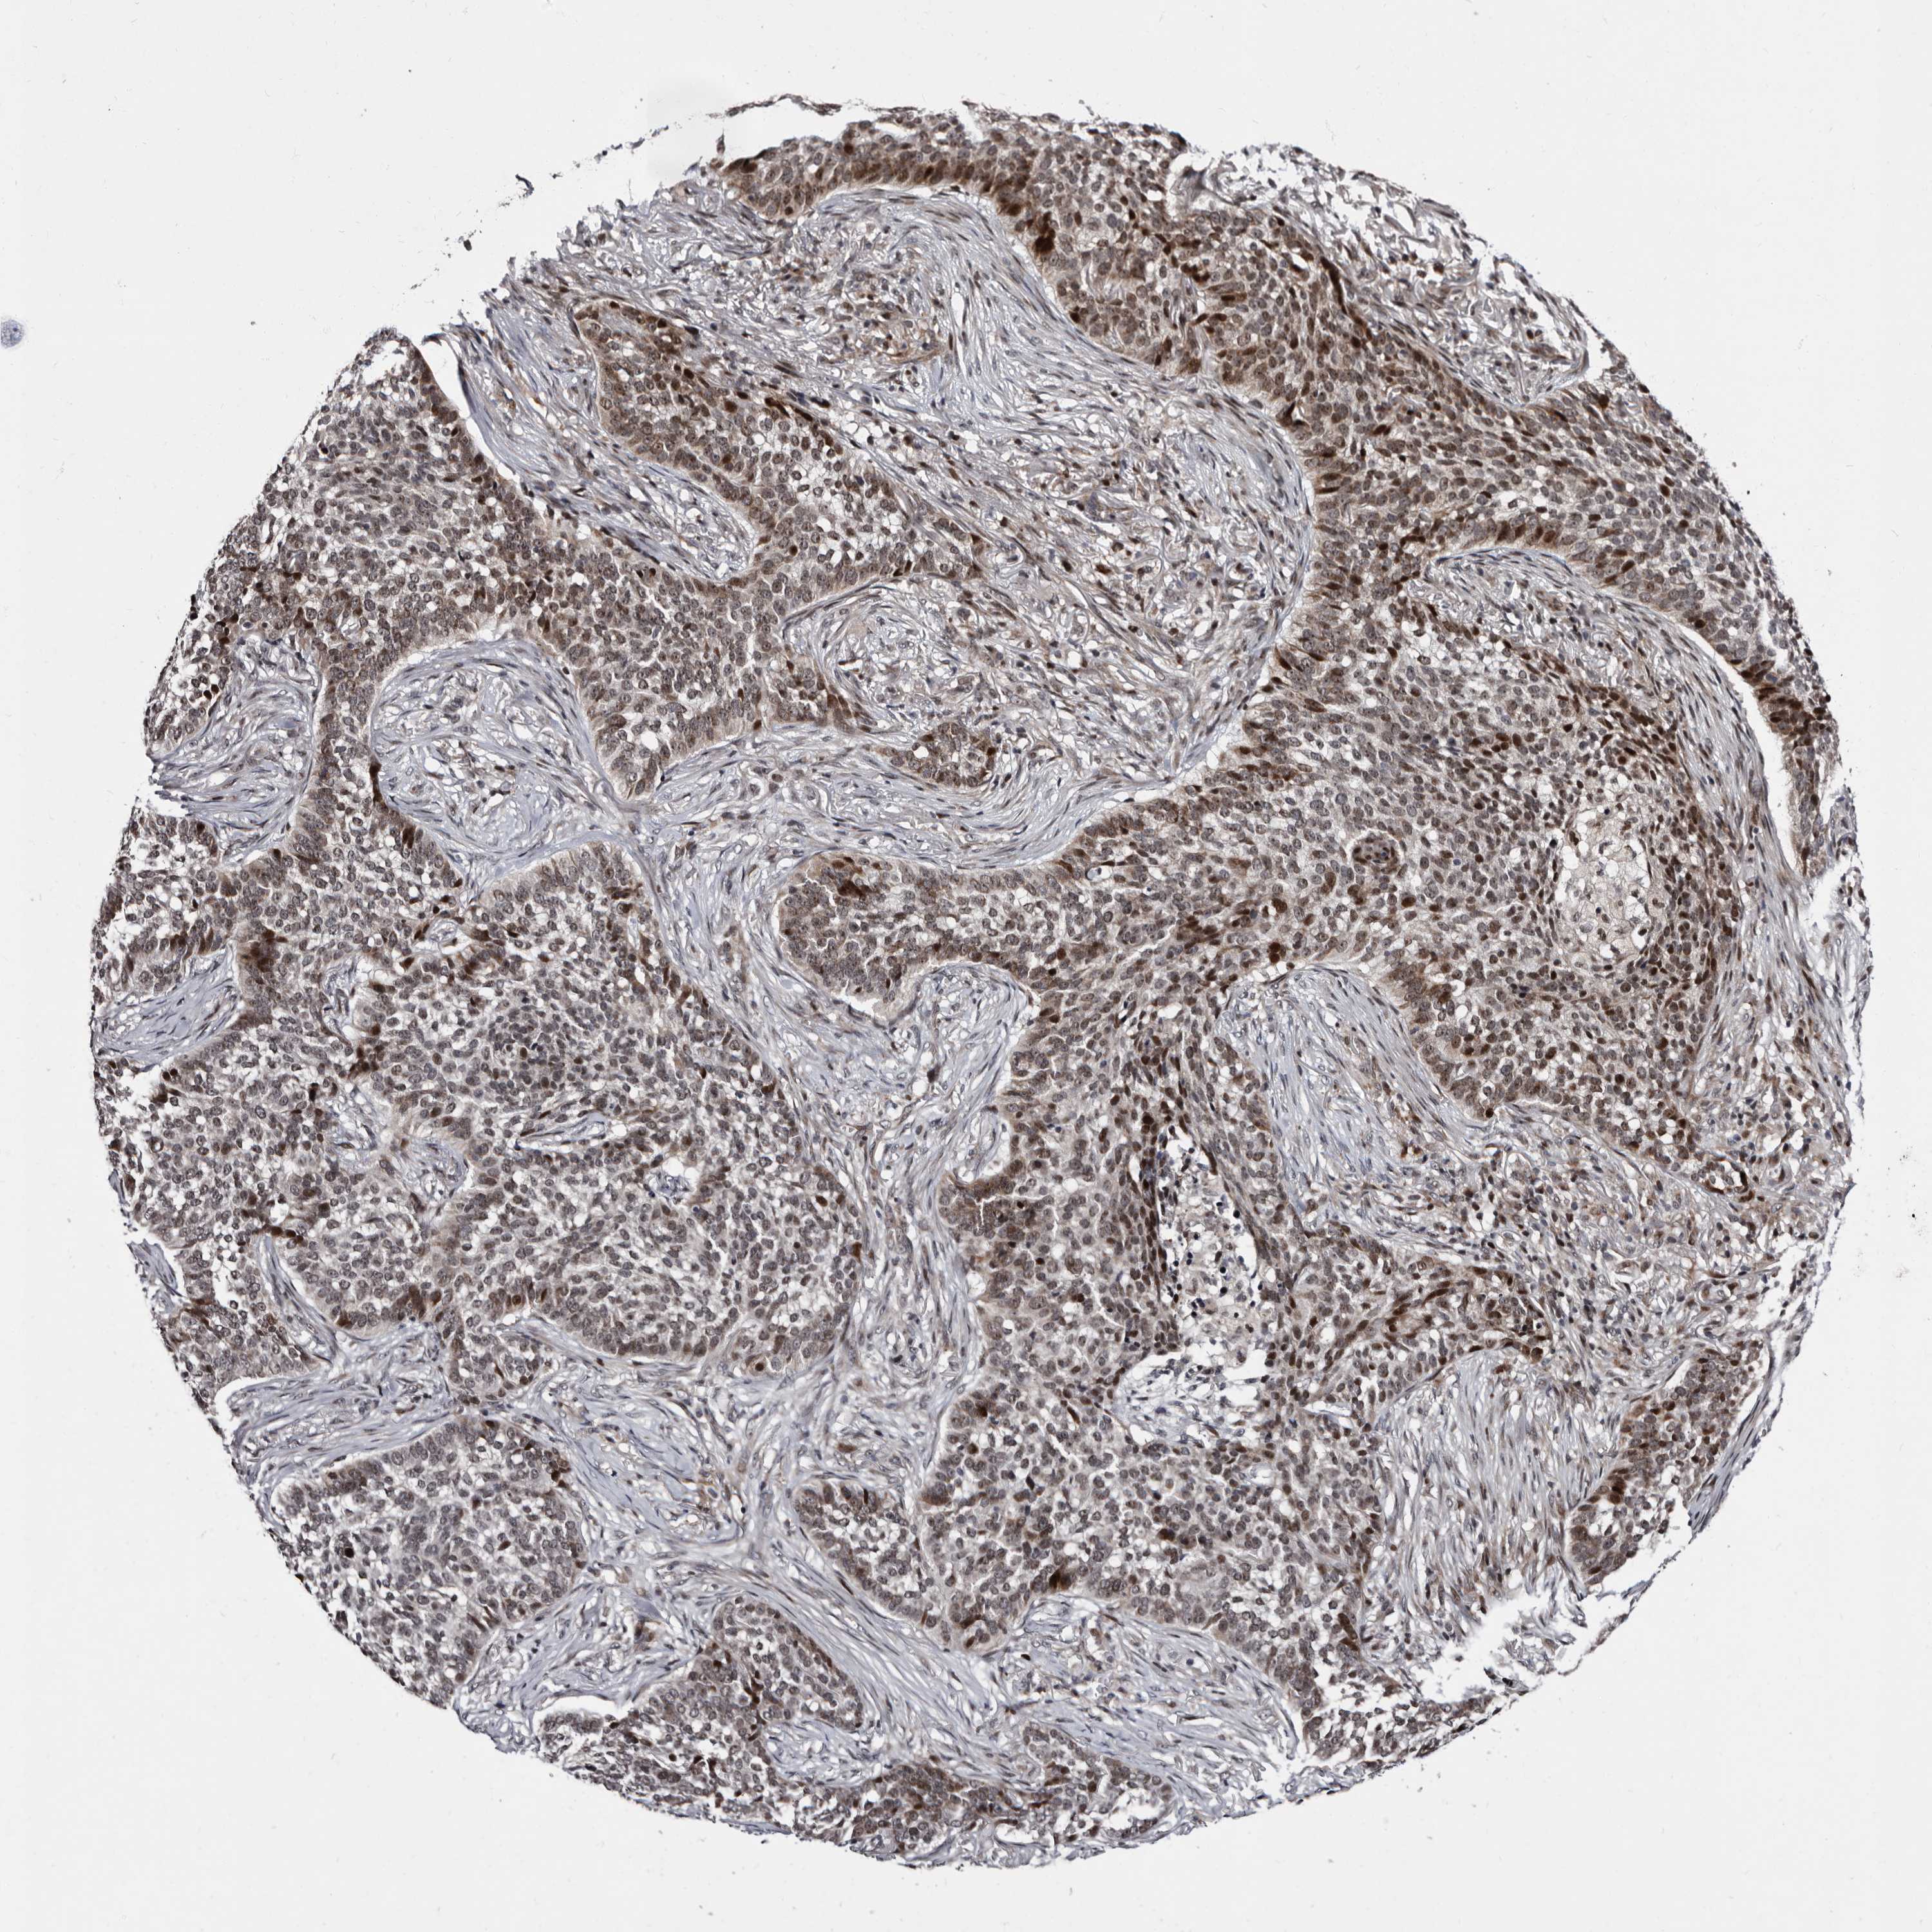

SKIN CANCER - Protein expressioni

A mouse-over function shows sample information and annotation data. Click on an image to view it in a full screen mode. Samples can be filtered based on level of antibody staining by selecting one or several of the following categories: high, medium, low and not detected. The assay and annotation is described here.

Each image is clickable and will lead to virtual microscopy that enables deeper exploration of all samples and also displays staining intensity scores, fraction scores and subcellular localization as well as patient and tissue information for each sample.

Antibody HPA025690

Staining

High

Intensity

Strong

Quantity

>75%

Location

Cytoplasmic/membranous,nuclear

Squamous cell carcinoma, NOS